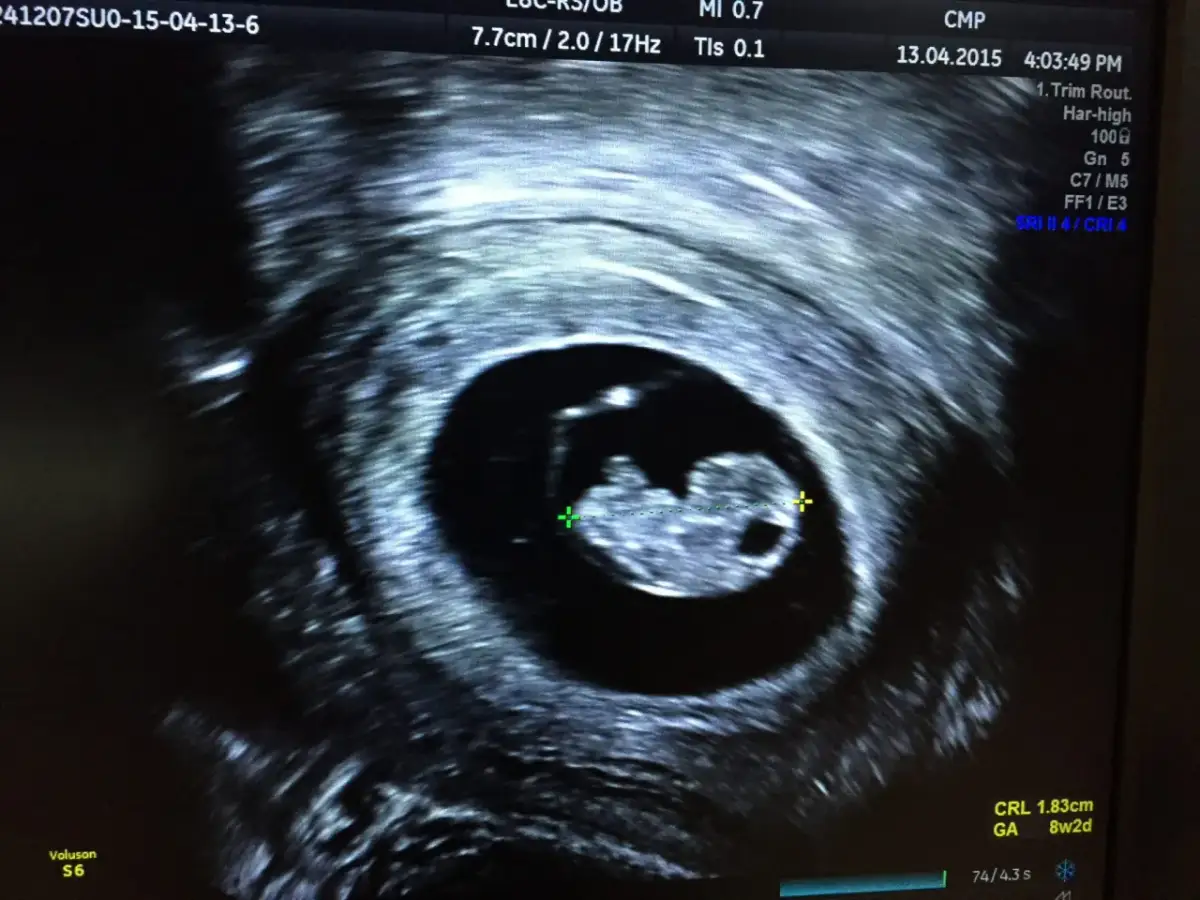

To jeden z najbardziej wyczekiwanych momentów około 5-6. tygodnia ciąży na monitorze USG pojawia się sam zarodek. Jest on na początku bardzo mały, ale jego obecność jest już wyraźnie widoczna. Prawdziwym przełomem jest jednak uwidocznienie i rejestracja czynności serca płodu (FHR - fetal heart rate), co zazwyczaj ma miejsce między 6. a 7. tygodniem ciąży. Bicie serca jest najpewniejszym potwierdzeniem, że ciąża jest żywa i rozwija się wewnątrzmacicznie. W tym okresie lekarz zaczyna również mierzyć zarodek, określając jego długość jako wymiar ciemieniowo-siedzeniowy (CRL - crown-rump length). Jest to najdokładniejsza metoda datowania ciąży w pierwszym trymestrze, pozwalająca precyzyjnie określić wiek ciążowy i przewidywany termin porodu.

Wymiar ciemieniowo-siedzeniowy (CRL) to długość zarodka mierzona od jego czubka głowy (ciemienia) do nasady pośladków (końcówki siedzeniowej). Jest to najbardziej wiarygodny parametr do określenia wieku ciąży w pierwszym trymestrze, czyli zazwyczaj do około 12-13 tygodnia. Istnieją precyzyjne tabele i algorytmy, które pozwalają lekarzowi na podstawie tej jednej miary z dużą dokładnością określić, w którym tygodniu ciąży znajduje się pacjentka, a co za tym idzie oszacować przewidywany termin porodu. CRL jest również ważnym wskaźnikiem prawidłowego rozwoju zarodka.